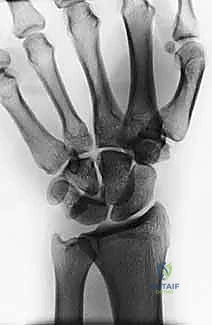

- Perilunate Dislocations: On PA, observe disruption of Gilula's lines and the lunate assuming a triangular, rather than trapezoidal, shape. On the lateral view, the concentricity of the "C's" (distal radius, lunate, capitate) is lost, indicating dorsal dislocation of the capitate from the lunate fossa.

Figure 3A: AP view of a perilunate dislocation, demonstrating loss of Gilula's lines.